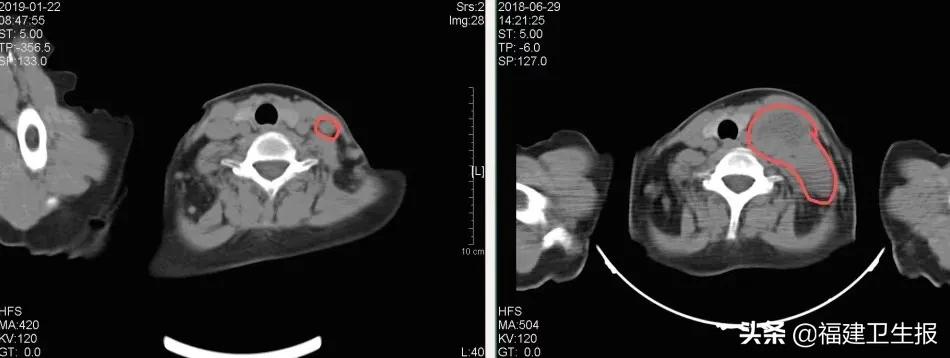

最终,采用射波刀立体定向放射治疗系统实施该放疗方案,张阿姨的腰背痛症状就明显缓解并康复,1个月之后复查发现腹膜后的转移病灶完全消失,5个月后左锁骨上病灶明显缩小。 值得庆幸的是,随访至今近3年,张阿姨仍然健康生活。

3D-Lattice计划中的靶区(红色)及处方剂量线(蓝色)

锁骨上的病灶,左图为放疗后5月余明显缩小,右图为放疗前